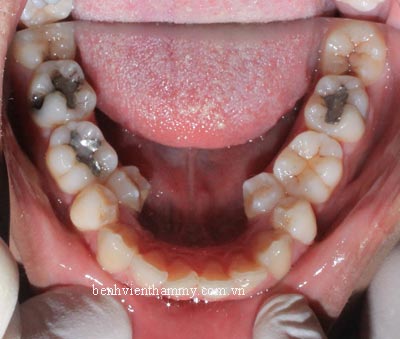

(Hình ảnh kết thúc điều trị sau 26 tháng)

Với chúng tôi thì không hài lòng với kết quả như thế.Chúng tôi liên tục cập nhật kiến thức và kinh nghiệm liên tục và hoàn toàn có thể tự tin thực hiện cho răng bạn tốt hơn như thế.

(Thực hiện bởi bác sĩ chuyên khoa cấp I chỉnh hình răng hàm mặt-Phạm Việt Hùng-nha khoa thẩm mỹ AVA)